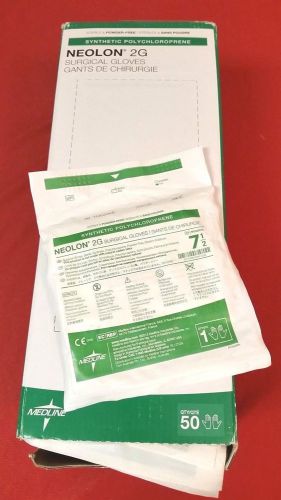

(50) New Medline Surgical Gloves Neolon 2G Synthetic Medical Home Work Size 7.5